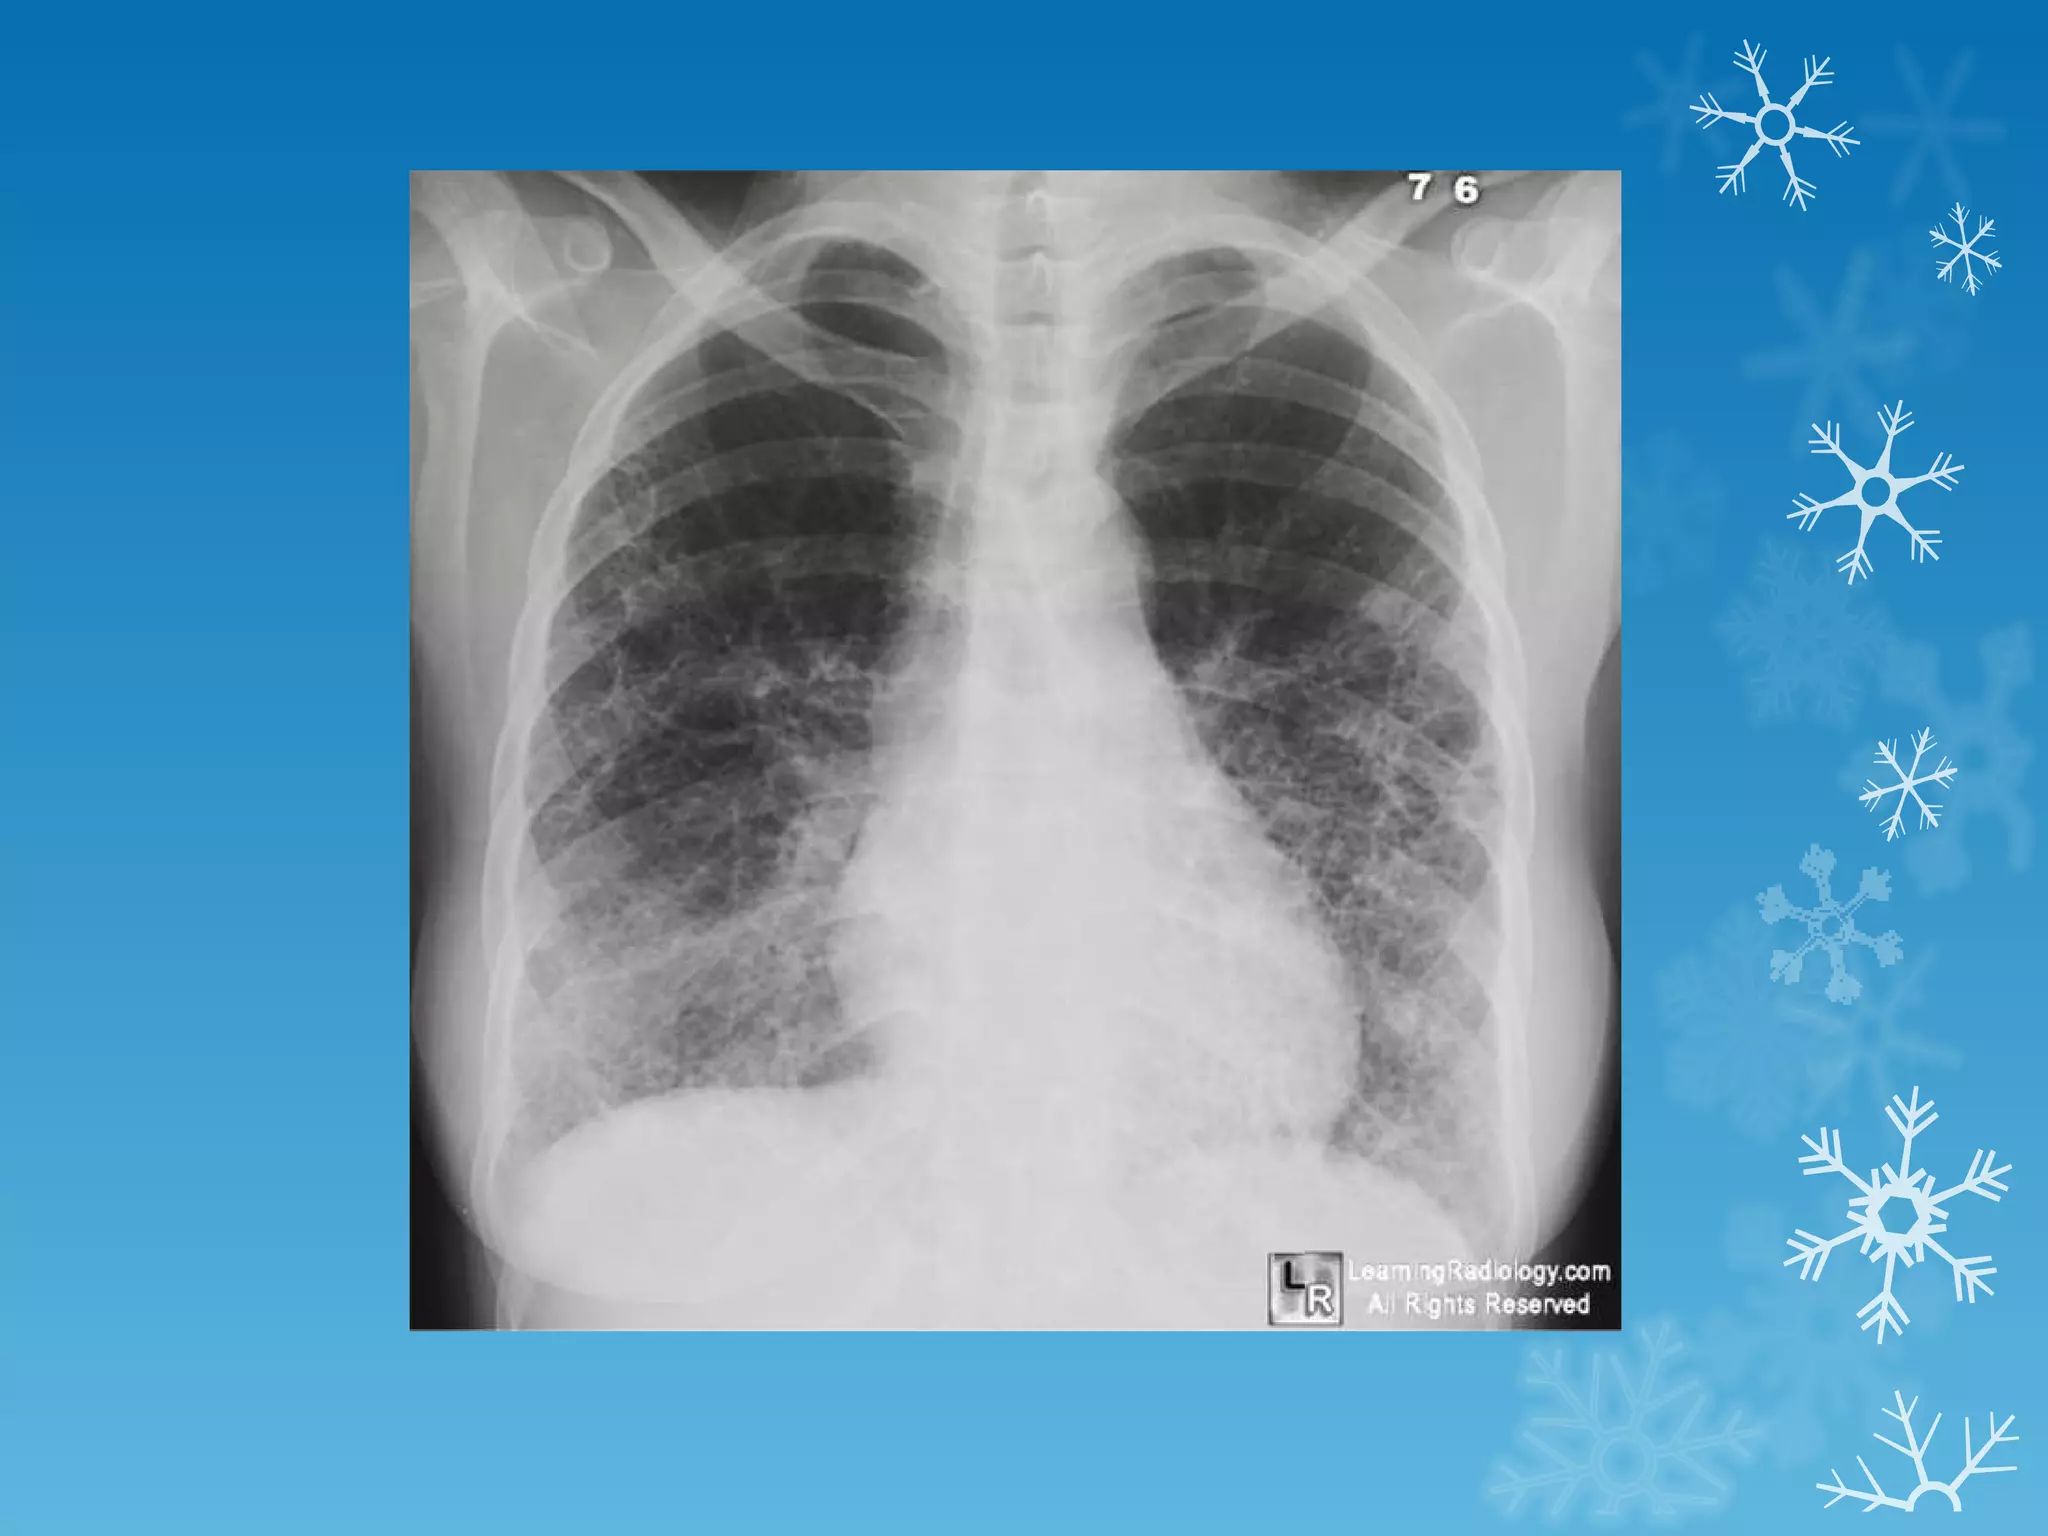

This document discusses chest x-ray interpretation and provides guidance on evaluating x-rays. It explains that tissue density determines how an x-ray beam penetrates, with denser tissues appearing whiter and less dense tissues appearing blacker. It also outlines different chest x-ray views and factors to consider like patient orientation, age, gender, and rotation. Abnormalities are described as appearing too white, too black, too large, or in the wrong place. The document stresses a systematic approach of identifying, localizing, describing lesions, and providing differential diagnoses.